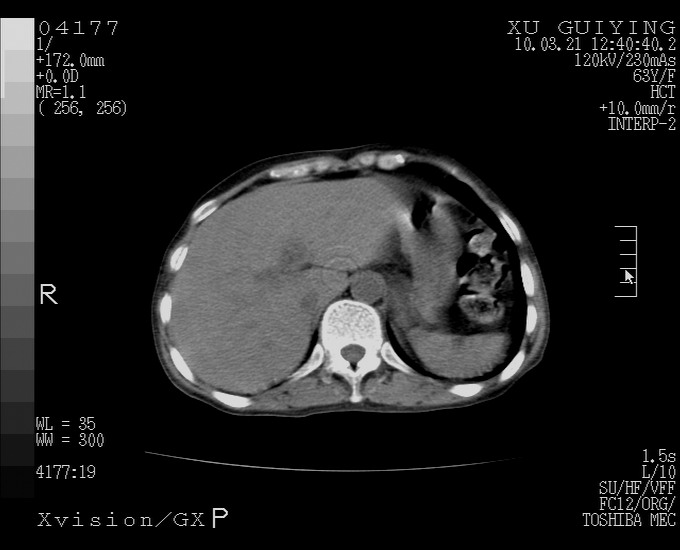

怎么没有增强呢?胆囊那么大,密度有些高啊。

慢性胆囊炎,胆囊占位不排除,建议增强或彩超。

考虑胆囊炎 不除外泥沙样结石

胆囊体积增大,胃窦壁增厚

胆囊体积增大

胆囊体积增大,密度不均匀,结石不除外;胃壁增厚,考虑胃癌,建议增强。

胆囊体积增大 ,建议超声检查。

胆囊体积增大,密度增高,较均匀,外缘也较光滑,应考虑胆囊炎。因为胃未充盈,不好说壁增厚。肝左叶及脾门处见低密度灶,有可能是血管瘤,不排除囊肿。建议超声检查或强化。

胆囊增大,原因待查。

这就是江湖人称的“内科黄疸”, 肝内胆汁淤积症(ic)?